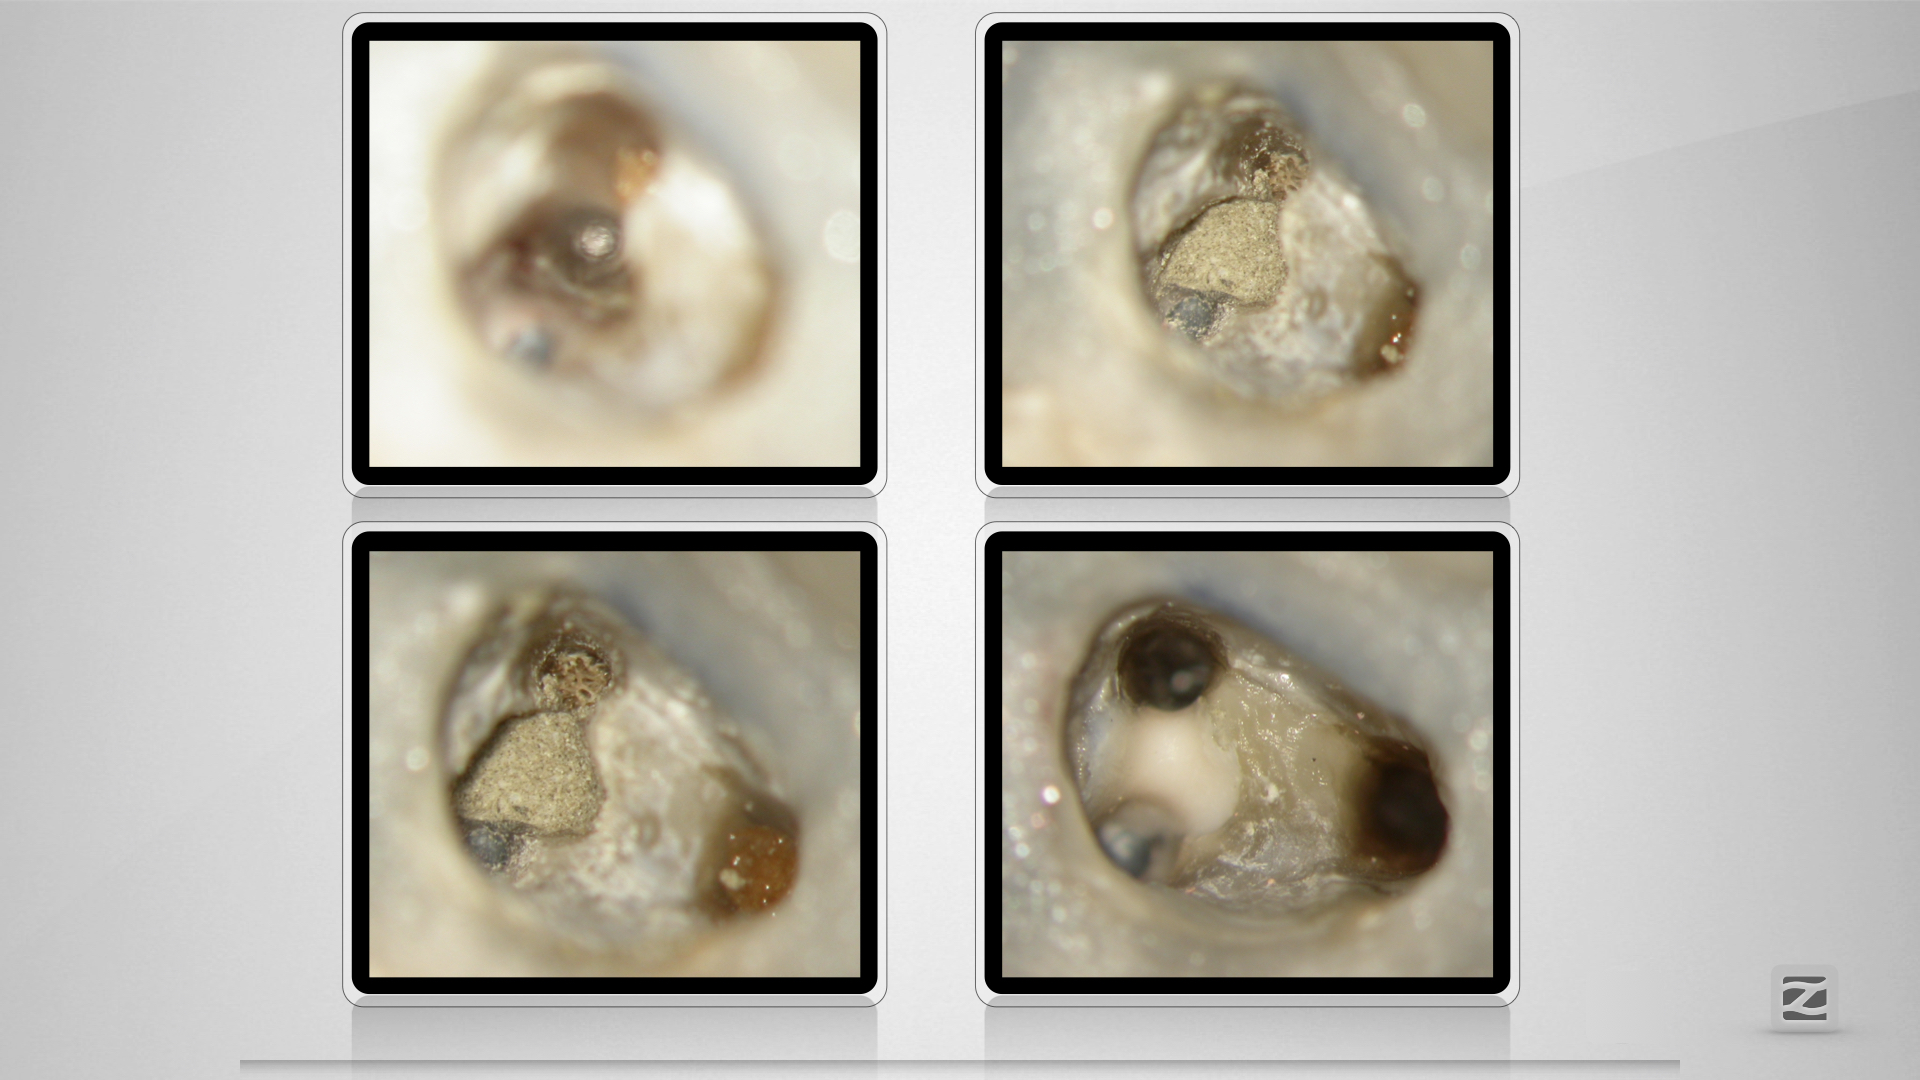

Fast getroffen ist auch vorbei!